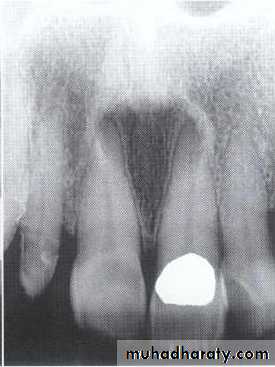

A: Odontogenic fibroma

B,C,D:Odontogenic myxoma.Odontogenic Adenomatoid Tumor (OAT)